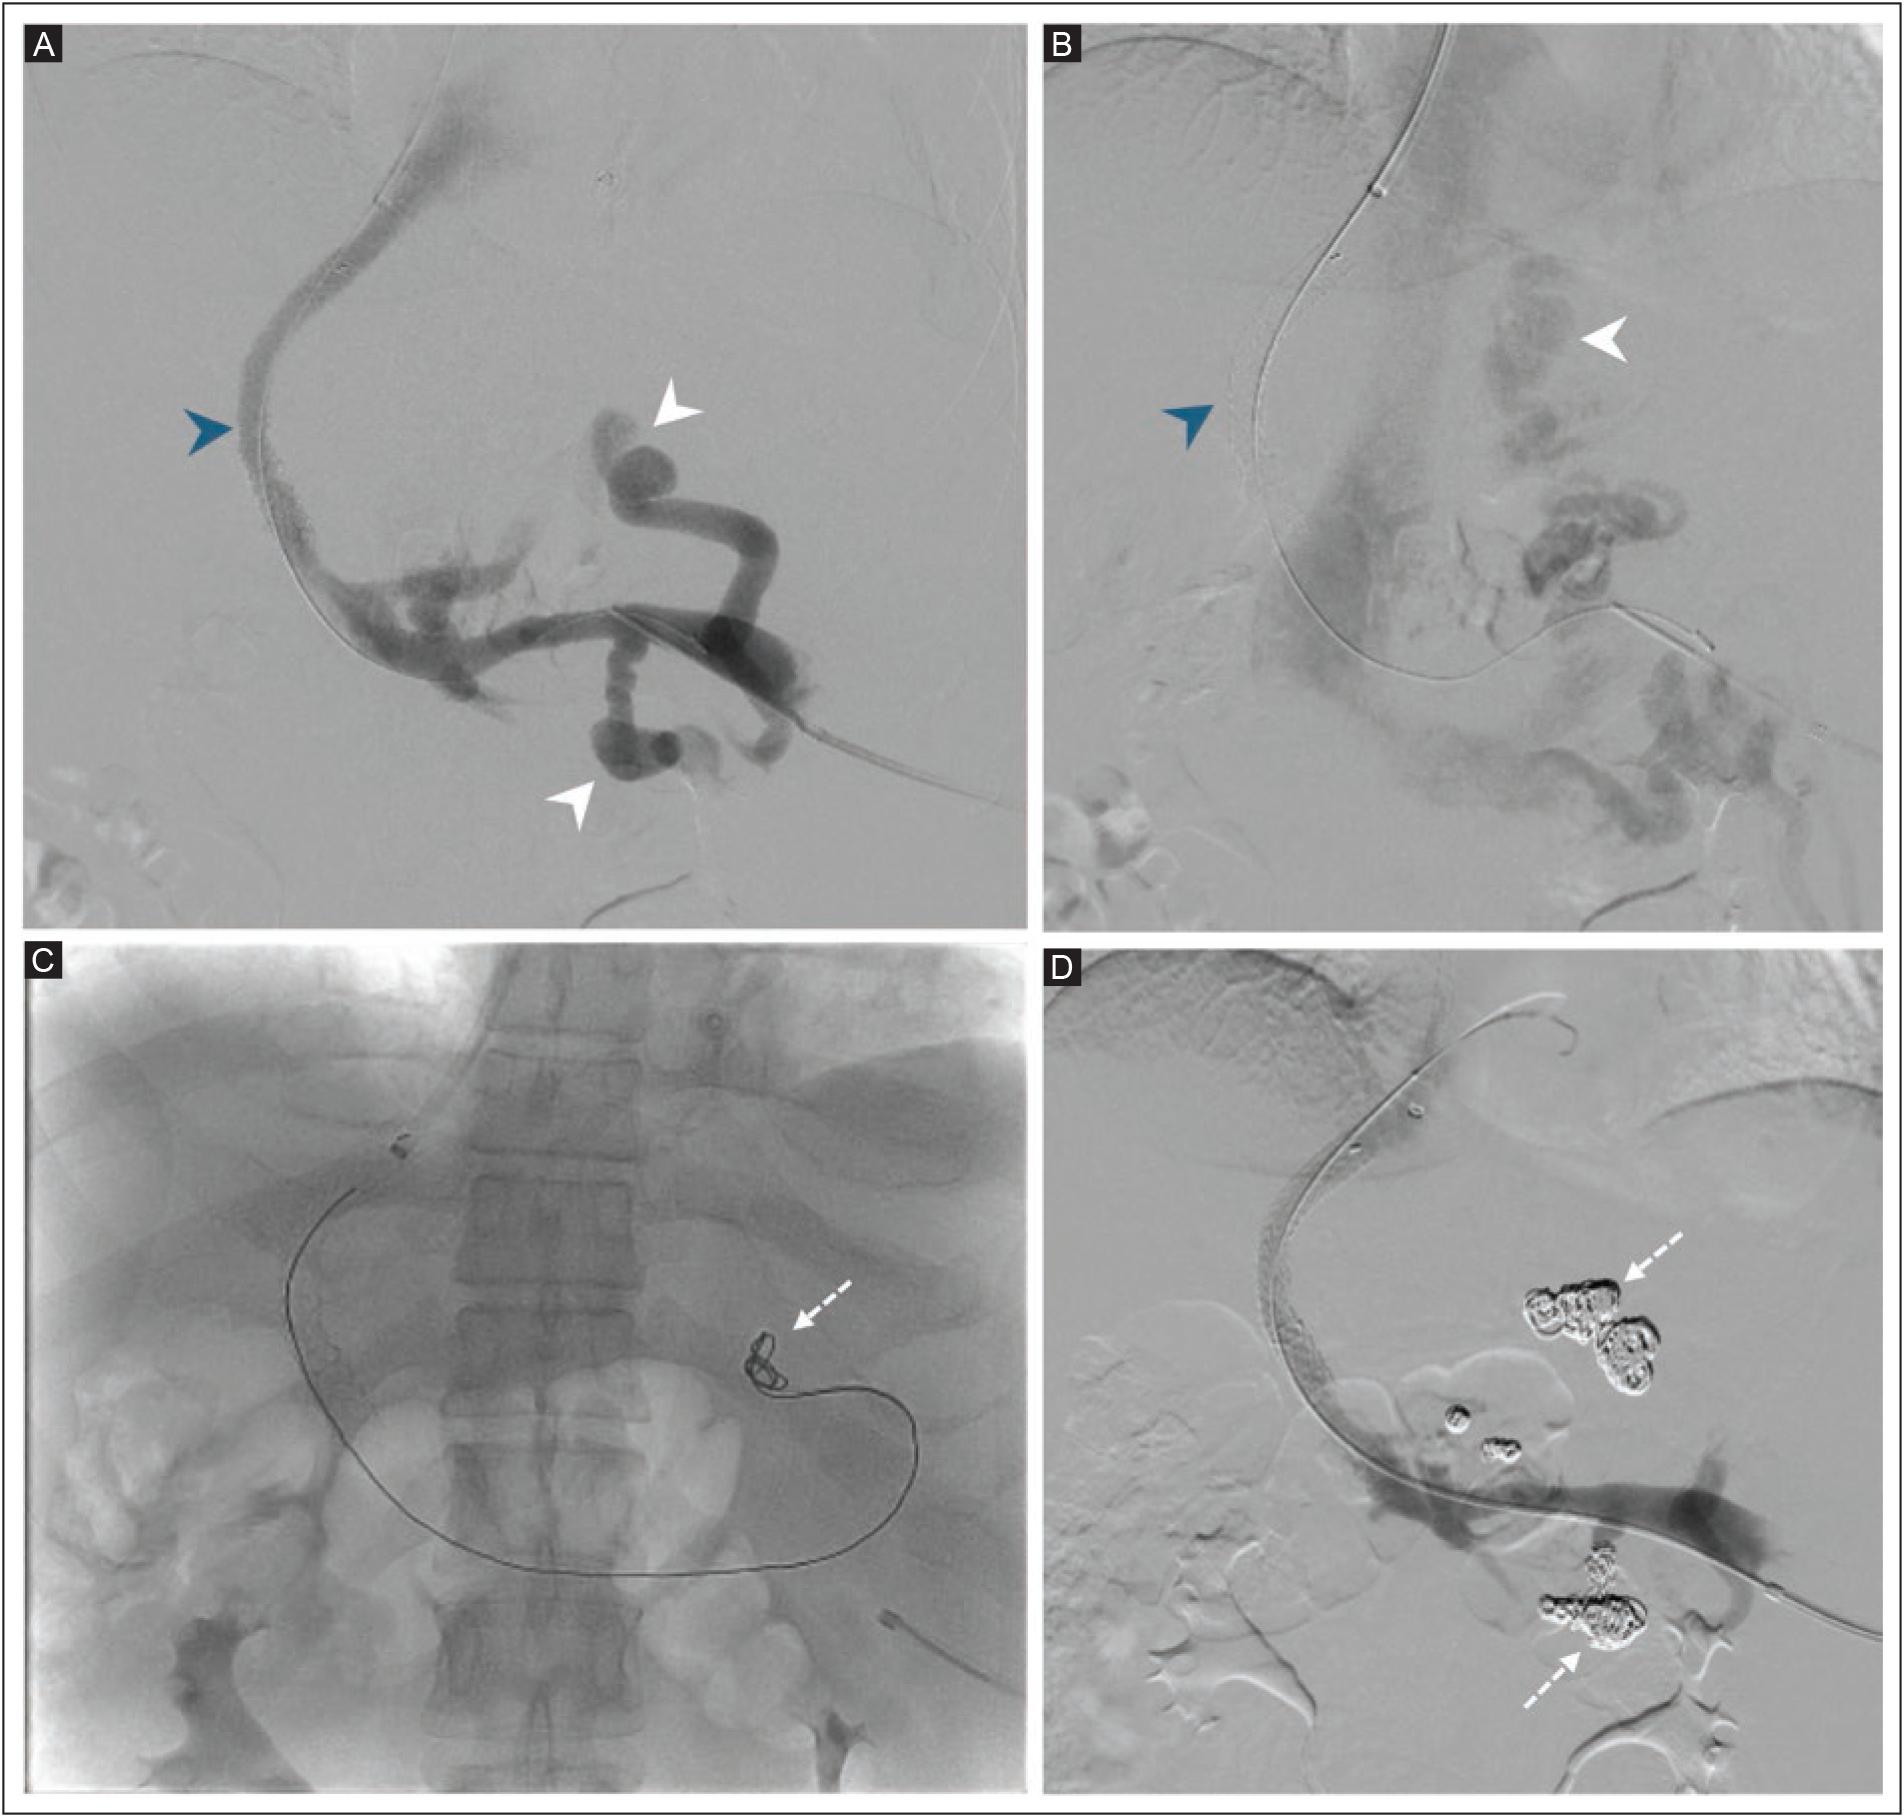

All TIPS procedures were performed with a RUPS-100 Transjugular Liver Access Set (Cook Medical, Bloomington, IN, USA). The corrected sinusoidal pressure was calculated as the difference between the wedged hepatic venous pressure (WHVP) and the free hepatic venous pressure, with WHVP determined in the right hepatic vein by advancing the sheath or catheter until contrast injection produced no venous reflux. Under fluoroscopic guidance, the intrahepatic puncture was directed from the right hepatic vein towards the right portal vein. Splenoportography and sizing of the shunt were performed with a 4-5F pigtail catheter, followed by tract predilatation with 6-8 mm angioplasty balloons. Bare-metal stents were used from 2004 to 2011; a Viatorr™ expanded polytetrafluoroethylene (ePTFE)-lined stent-graft endoprosthesis (W.L. Gore & Associates, Newark, DE, USA) has been used since 2012. After placement of the stent, 8-10 mm high-pressure angioplasty balloons were used until the PSPG between the portal and hepatic veins reached the target value. The inferior vena cava and right atrial pressures were also measured before sheath removal. Hemostasis was achieved by manual compression, and large-volume paracentesis was performed immediately after the procedure in patients with ascites. Figure 1 shows digital subtraction angiography after performing a TIPS in a 39-year-old man with cirrhosis and variceal bleeding. A covered stent and hepatofugal flow with multiple venous collaterals, including gastric and renal shunts, are seen. Trans-TIPS embolization of the fugal shunts was performed with helical coils and ethanol + Gelfoam®. A team of three interventional radiologists with 31 years (MCM), 11 years (FPG), and two years (SKJ) of experience performed the TIPS procedures.

Figure 1 Digital subtraction angiography after TIPS placement in a 39-year-old man with cirrhosis and variceal bleeding. A-B: a covered stent (blue arrowheads) with hepatofugal flow, with multiple venous collaterals, and gastric and renal shunts are seen (white arrowheads). C-D: trans-TIPS embolization of the fugal shunts performed with helical coils (dashed arrows) and ethanol + Gelfoam®.